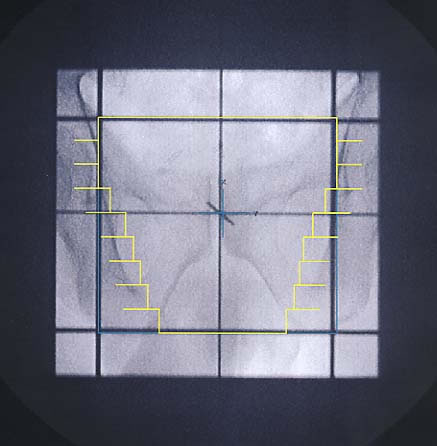

Prostatakarzinom: Simulationsbild